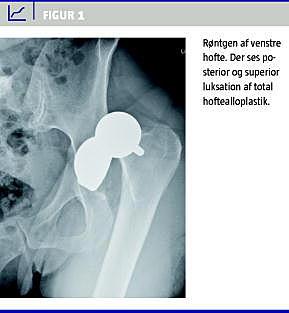

En 62-årig kvinde blev indlagt på psykiatrisk afdeling under diagnosen svær depression. Patienten havde to år tidligere fået total hoftealloplastik på venstre side pga. osteoartrose. Protesen var velplaceret, og der havde ikke været fortilfælde med luksation. Op til indlæggelsen havde patienten haft dårlig appetit og nedsat aktivitetsniveau, hvilket havde resulteret i et vægttab på ti kilo. Ved indlæggelsen blev vægten målt til 63,4 kg. Patienten blev straks opstartet i antidepressiv medicin, men pga. sværhedsgraden af depressionen ordinerede man efter ca. en uge elektrokonvulsiv terapi (ECT). Tre dage efter modtog patienten sin første ECT. Patienten fik 200 mg thiopental intravenøst efterfulgt af 35 mg suxamethon, også intravenøst. Patienten blev efterfølgende rutinemæssigt hyperventileret i ca. et minut. Grundet problemer med for høj impedans ved testningen af det elektroniske kredsløb forsinkedes selve strømafgivelsen i ca. et halvt til et minut. Efter strømafgivelsen fik patienten et meget kraftigt klinisk generaliseret tonisk-klonisk krampeanfald med elektroencefalografi (EEG)-aktivitet i 48 sekunder. Straks efter behandlingen klagede patienten over smerter i venstre hofte, og et røntgenbillede af venstre hofte viste superior og posterior luksation af hoftealloplastikken (Figur 1 ). Hofteprotesen blev efterfølgende reponeret af ortopædkirurg.